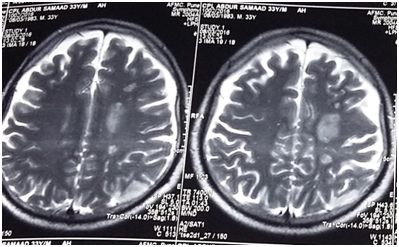

After ensuring no active bleeding and patient was hemodynamically stable he was extubated uneventfully and shifted to Intensive care unit. Post op CT Angiography done on same day after three hours revealed acute thrombosis at left distal cervical, petrous, and cavernous ICA. Bony defects/dehiscence has be seen in posterolateral aspect of sphenoid sinus in relation to course of ICA. B/L the gap between midline of sphenoid and the ICA was measuring less than 4mm on left and 5mm on right side. Left sphenoid was also smaller than the right side. No evidence of early ischemic changes noted in brain parenchyma. No active contrast leak or extravasations seen. There was adequate collateral supply from opposite ICA and circulation flow was adequate in circle of Willis and posterior fossa (Figure 1). In view of adequate brain circulation and a localized thrombus in injured ICA the decision was taken in consultation with interventional radiologist and neurologist to manage it conservatively rather opting for any endovascular stent option.

Figure 1 Immediate post op CT Angiography showing no ischemia or leakage of contrast.